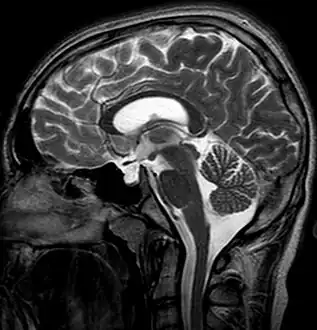

Empty sella- MRI Scan of the brain, sagittal T2-weighted

Empty sella in MRI